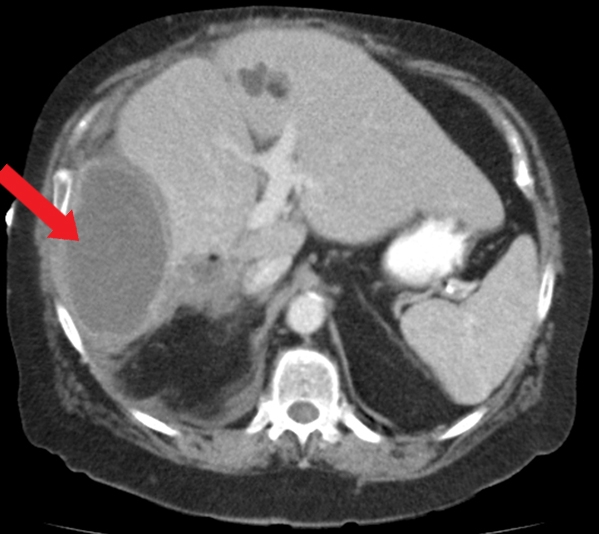

Entamoeba Histolytica

This patient who recently emigrated from Mexico has abdominal pain, fever, leukocytosis, and a liver abscess on imaging. Given his young age, the absence of animal contact, and history of dysentery a few months ago, the most likely etiology is an amebic abscess caused by the intestinal protozoan, Entamoeba histolytica. The differential diagnosis includes pyogenic (bacterial) abscess and hydatid cyst caused by Echinococcus. However, bacterial abscesses generally occur in older patients with underlying medical conditions (eg, diabetes or hepatobiliary disease) or following peritonitis. Echinococcus cysts are not associated with fever, are frequently asymptomatic, and require contact with animals (eg, dogs, sheep); eosinophilia can occur if there is antigenic material leakage.

E histolytica infection (amebiasis) is most common in areas of poor sanitation. Most infected patients are asymptomatic but those with symptoms often develop dysentery. Extraintestinal infection is rare and generally limited to the liver, where the organisms form an abscess. The presentation is similar to a bacterial pyogenic abscess, including fever and right upper quadrant pain. Elevated alkaline phosphatase is common and elevated transaminases may be seen. Imaging typically shows a solitary lesion, generally found in the right lobe of the liver. Serologic testing for E histolytica antibodies confirms the diagnosis. Stool microscopy is insensitive by the time a liver abscess has formed (generally months after the initial infection).

Treatment of amebic liver abscess is with metronidazole (>90% cure with oral therapy). A luminal agent (ie, paromomycin) is also required to eradicate intestinal colonization. Drainage is not recommended routinely due to the high response rate to appropriate antiamebic therapy and the risk of rupture into the peritoneum. Drainage is reserved for mass effect, imminent rupture, or when the diagnosis remains uncertain or the patient is not improving with therapy. In contrast, large hydatid cysts due to Echinococcus can be treated with aspiration in combination with albendazole (Choice C).